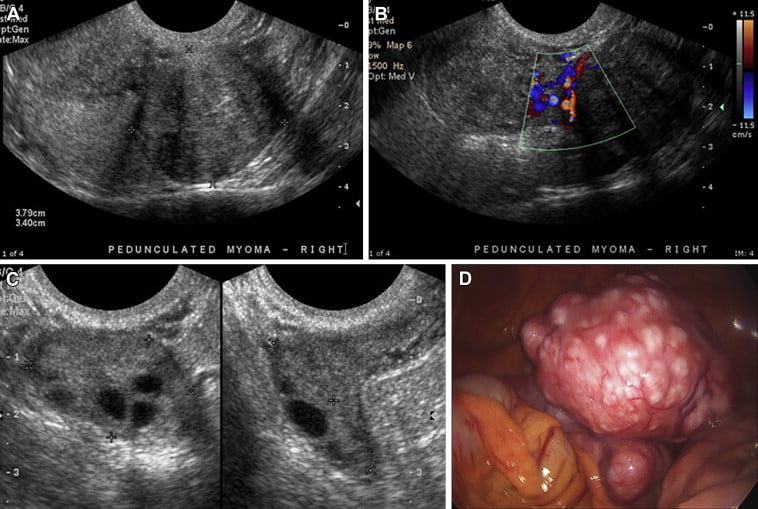

Miyomlar, genellikle rutin jinekolojik muayenelerde ultrason yardımıyla teşhis edilir. Ultrason, miyomların boyutunu, yerleşimini ve sayısını belirlemede etkili bir yöntemdir. Büyük veya karmaşık miyomların teşhisi için ise Manyetik Rezonans (MR) gibi ileri görüntüleme yöntemleri kullanılabilir. Bu yöntemler, miyomların yapısını ve büyümesini detaylı bir şekilde incelemeyi sağlar.

Miyomlar genellikle rutin jinekolojik muayeneler sırasında ultrason yardımıyla tespit edilir. Gerekli durumlarda MR gibi ileri görüntüleme yöntemleri de kullanılabilir. Bu yöntemler, miyomların boyutunu, sayısını ve yerleşimini detaylı bir şekilde gösterir